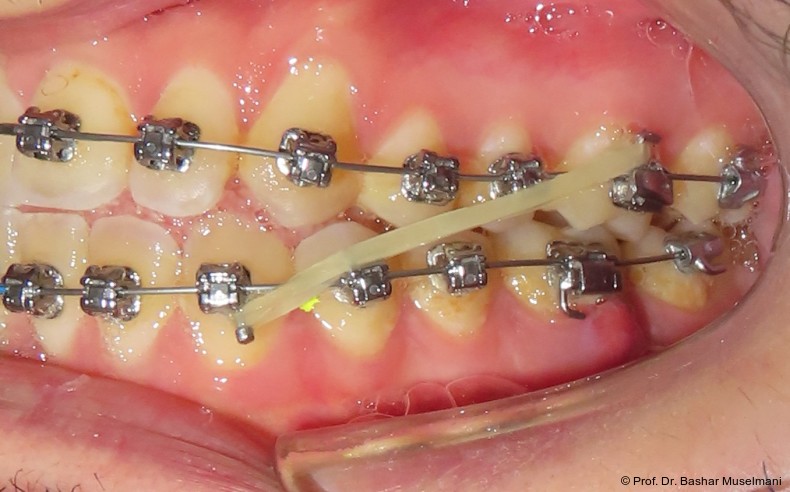

Zur sagittalen Korrektur wurden intermaxilläre Klasse III-Gummizüge eingesetzt.

Zu Beginn der Nivellierungsphase wurden in beiden Kiefern 0.013" CuNiTi-Bögen eingesetzt (Abb. 4a–e).

Bogensequenz und mechanische Umsetzung

Der Bogenwechsel erfolgte in einem standardisierten Intervall von acht Wochen. Die Sequenz war in beiden Kiefern weitgehend identisch und wie folgt aufgebaut:

• 0.013" CuNiTi (OK / UK)

• 0.016" CuNiTi (OK / UK)

• 0.018" CuNiTi (OK / UK)

• 0.014 x 0.0275" CuNiTi (OK / UK)

• 0.016 x 0.0275" Edelstahl (OK)

• 0.018 x 0.0275" CuNiTi (OK / UK)

• Abschlussbogen: 0.018 x 0.0275" TMA (OK/UK)

Diese Sequenz ermöglichte eine schrittweise Ausformung der Zahnbögen, eine kontrollierte Torque-Expression sowie eine präzise Feineinstellung in der Abschlussphase (Abb. 5a–e).